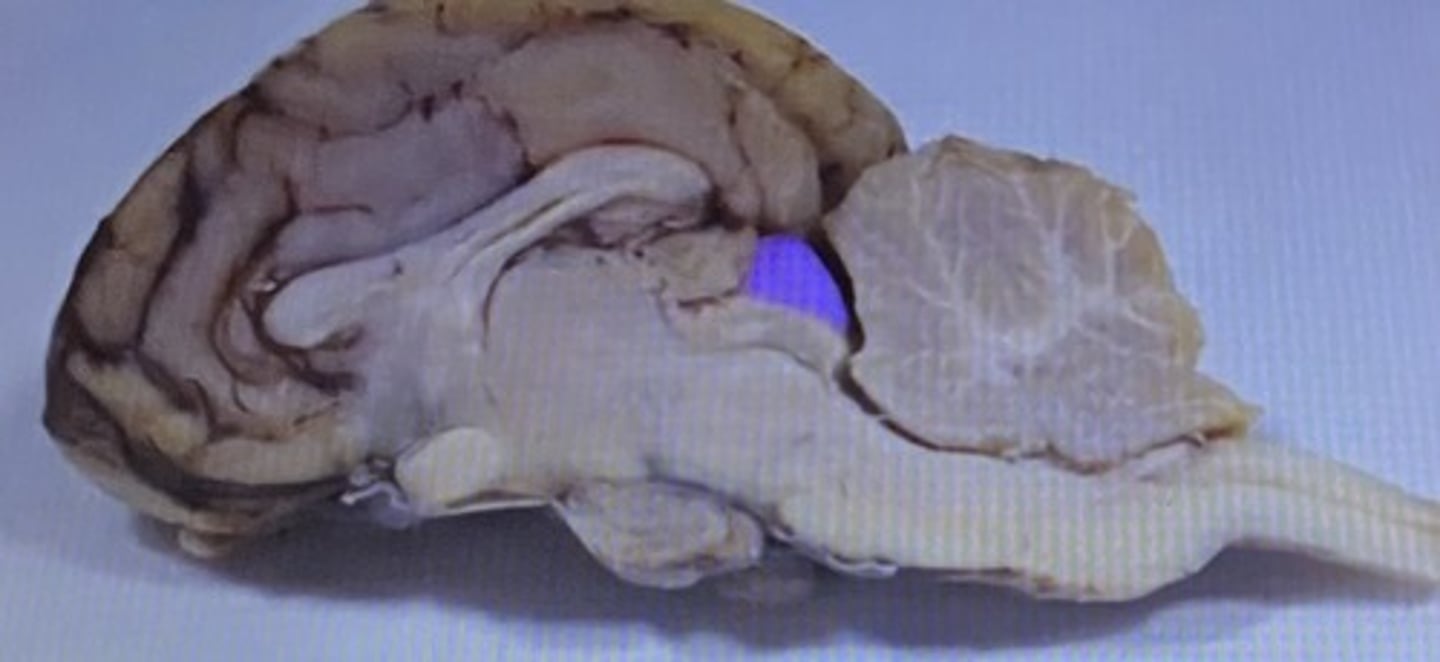

Frontal Lobe

Parietal Lobe

Temporal Lobe

Occipital Lobe

Cerebrum

Cerebellum

Arbor Vitae

Medulla Oblongata

Pineal Body/Gland

Corpus Callosum

Choroid Plexus

Fornix

Thalamus

Hypothalamus

Infundibulum

Pituitary Gland

Olfactory Bulb

Olfactory Tract

Superior Colliculus

Inferior Colliculus

Lateral Ventricle

Third Ventricle

Fourth Ventricle

Cerebral Aqueduct

Cerebrum

-conscious brain

Cerebellum

-coordinates muscles movements, muscle memory

Transverse Fissure

-separates cerebrum & cerebellum

Sheep Lateral Ventricle

-produces and contains cerebrospinal fluid

Sheep Fornix

Sheep Thalamus

-gateway to cerebral cortex

Sheep Hypothalamus

-located under the thalamus on human brain

-controls pituitary gland and autonomic centers of medulla oblongata

Sheep Pituitary Gland

Sheep Cerebral Cortex

-grey matter that contains neuron cell bodies

-site of the "conscious mind"

Sheep White Matter

-contains bundles of myelinated axons called "tracts" in CNS

Sheep Longitudinal Fissure

Sheep Corpus Callosum

Sheep Third Ventricle

sheep corpus callosum

Sheep optic chiasm

Sheep Pineal Gland

Sheep superior colliculus

Sheep Cerebellum

sheep 4th ventricle

Sheep Central Canal

Sheep Optic Chiasm

Sheep Pons